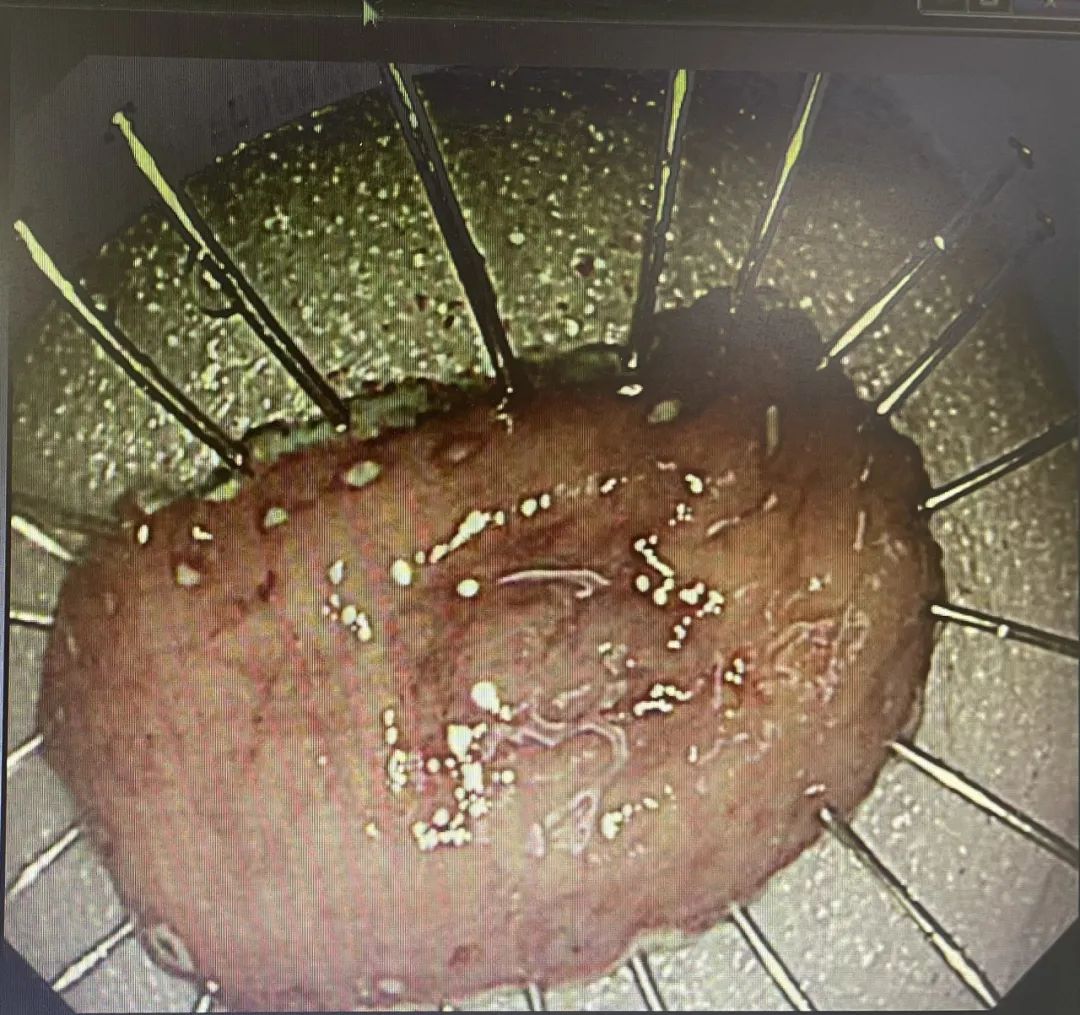

【技術(shù)領(lǐng)航】精準(zhǔn)篩查消化道早癌!早發(fā)現(xiàn)、早治療,90%消化道癌癥完全可以治愈

消化界有這樣一句話:“發(fā)現(xiàn)一例早癌,挽救一個生命,拯救一個家庭!”消化道癌癥防治的唯一出路為“三早”,即:早期發(fā)現(xiàn)、早期診斷、早期治療。世界衛(wèi)生組織(WHO)明確指出:早期發(fā)現(xiàn)是提高癌癥治療率的關(guān)鍵。只要早期發(fā)現(xiàn),90%的癌癥完全可以治愈!